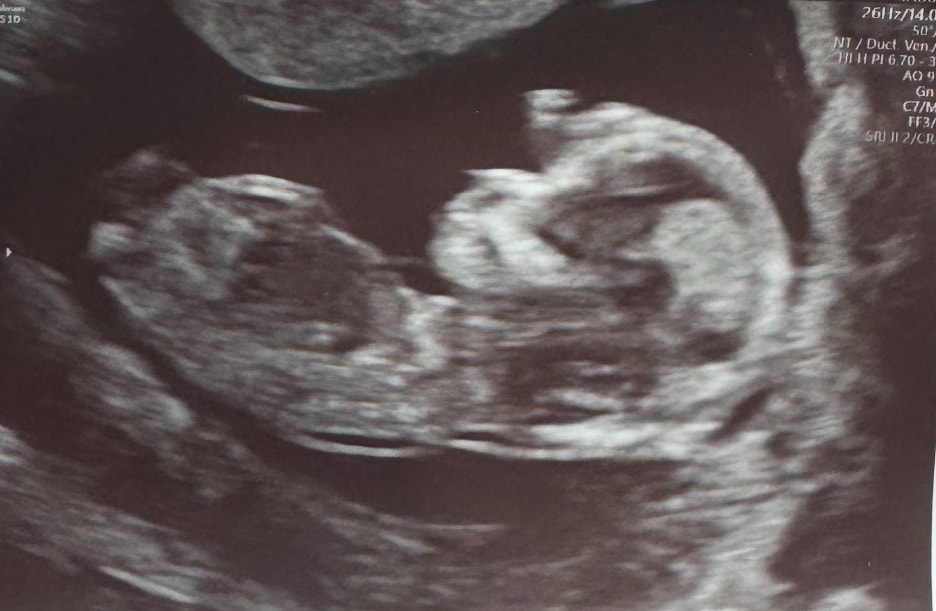

Мне кажется, Девочка

Так здОрово держит ручку на лбу 😅

Мне тоже кажется, что девчонка. Тазовая кость у мальчишек цельная, на УЗИ более четко выражена, а у девочек состоит из кусочков